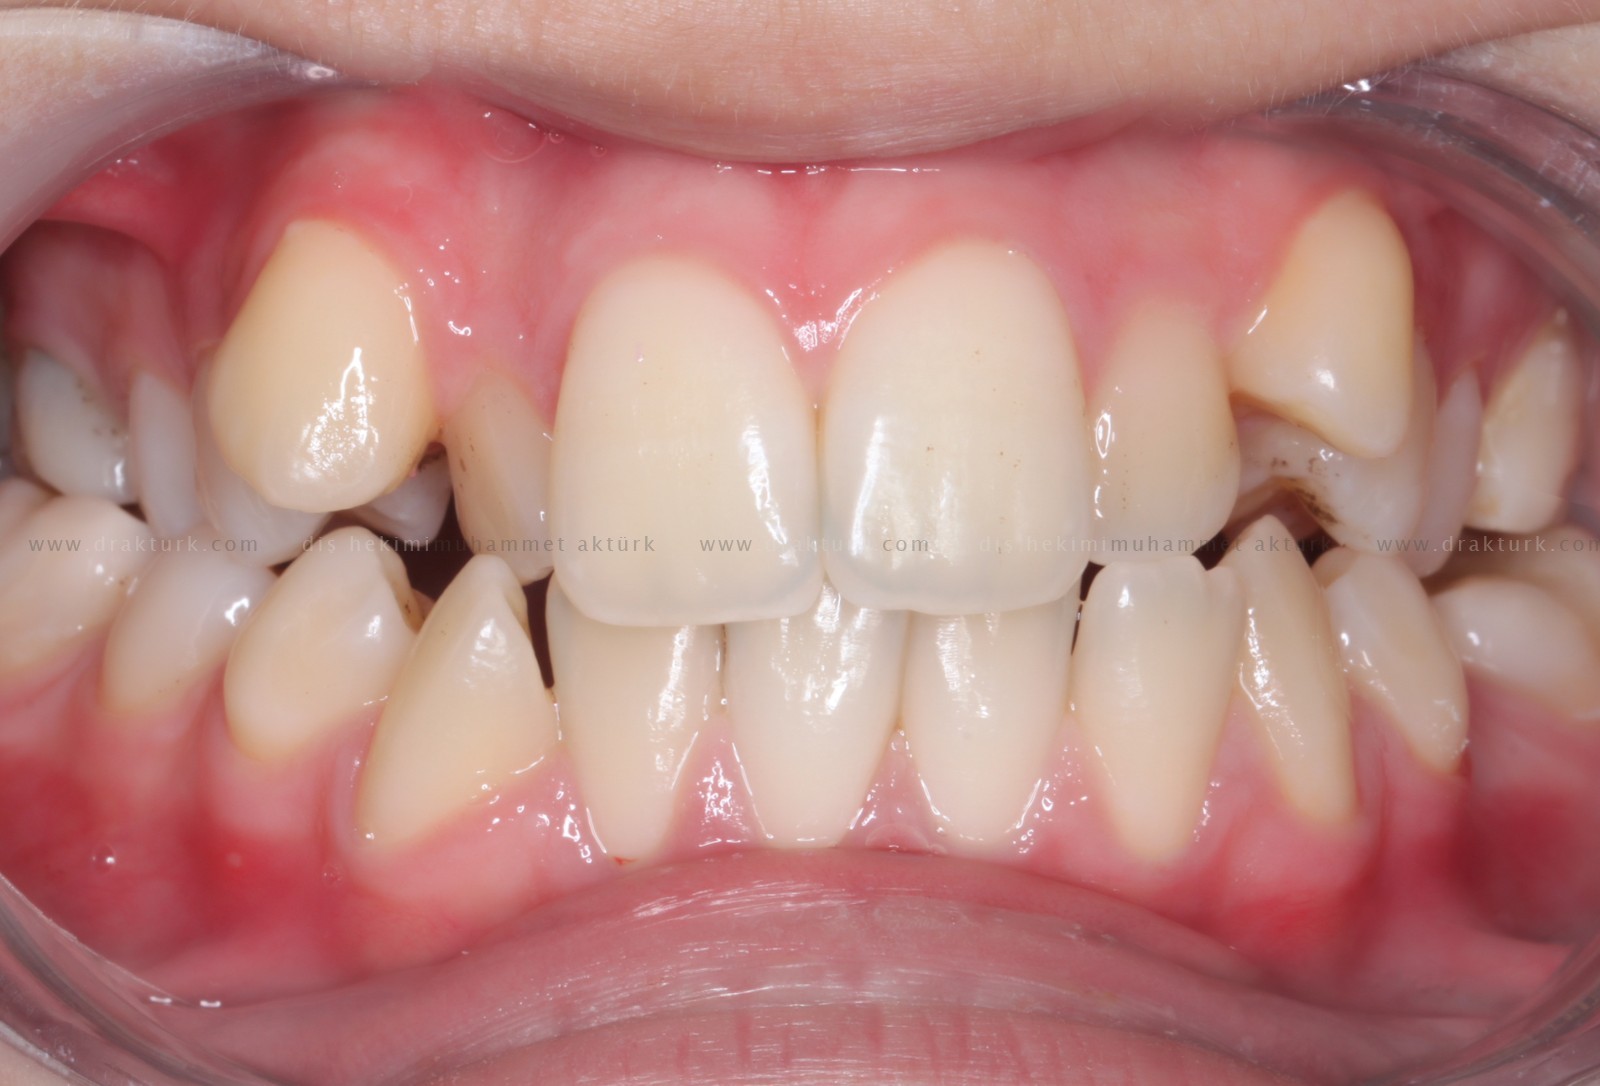

An example of the treatments we have done :

TREATMENT of ANTERIOR TOOTH FRACTURE WITH AESTHETIC COMPOSITE FILLING

Before